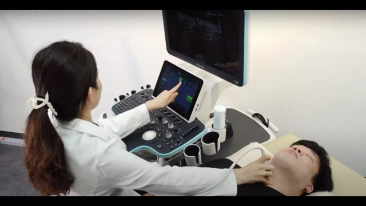

Resona 7

Nuove tendenze nellŌĆÖinnovazione dellŌĆÖecografia

Fin dalla sua fondazione Mindray esplora continuamente nuovi modi per migliorare l'affidabilit├Ā diagnostica. Equipaggiata con la pi├╣ rivoluzionaria tecnologia ZONE Sonography?, la nuova piattaforma ZST+ di Resona 7 porta la qualit├Ā dell'immagine ecografica ad un livello superiore con l'acquisizione per zone e l'elaborazione dei dati canale.

Oltre alla qualit├Ā delle immagini di livello eccellente, Resona 7 migliora anche le capacit├Ā di ricerca clinica il rivoluzionario V Flow per la valutazione emodinamica vascolare, e l'acquisizione piani pi├╣ intelligente dal set di dati 3D per la diagnosi del sistema nervoso centrale fetale. Combinando il pi├╣ intuitivo funzionamento multi-touch basato su gesti e tutte le caratteristiche cliniche essenziali, Resona 7 sta veramente portando nuove tendenze nellŌĆÖinnovazione dellŌĆÖecografia.